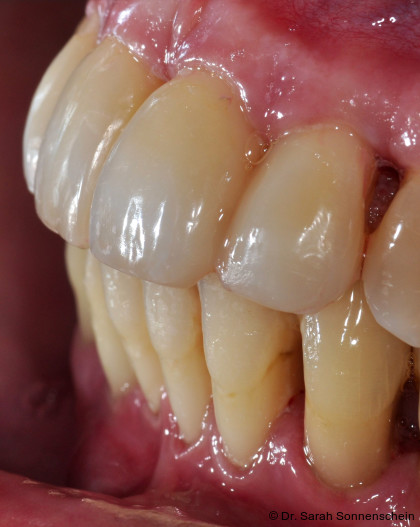

In den letzten Jahren hat sich auch die Zahnmedizin zunehmend digitalisiert. Mit Intraoralscannern können hochpräzise dreidimensionale Modelle der Kiefer und Zähne erstellt werden, auch vom parodontal geschädigten Gebiss.18 Es gehört heute zum zahnmedizinischen Standard, dass auf Basis von digitalen 3D-Modellen metallfreier zahnfarbener Zahnersatz wie Einzelzahnkronen oder Brücken aus Zirkoniumoxid (ZrO2) im subtraktiven Fräsverfahren hergestellt werden. Eine völlig neue Methode zur Herstellung von Zahnersatz oder zahnmedizinischen Hilfsteilen eröffnet sich mit der Möglichkeit, ZrO2 in speziellen 3D-Druckern erstellen zu können. Ein Vorteil gedruckter Konstruktionen liegt darin, dass die geometrischen Möglichkeiten nicht durch die Anzahl der Fräsachsen beschränkt ist. In einer aktuellen experimentellen Studie wurde gezeigt, dass bei der adhäsiven Zementierung von gedruckten ZrO2-Restaurationen eine ähnlich hohe Haftkraft erzielt werden kann, wie für gefräste Restaurationen.19 Durch die Anwendung dieser neuen Technik könnte es möglich sein, in Zukunft gut haftende, bruchstabile und ästhetisch hochwertige zahnfarbene Schienen im Labor herzustellen. Erste Vorversuche zu diesem Vorgehen (Abb. 4) zeigen vielversprechende Ergebnisse, und es ist mit Spannung zu erwarten, ob und wie sich diese Möglichkeit weiter entwickeln wird.